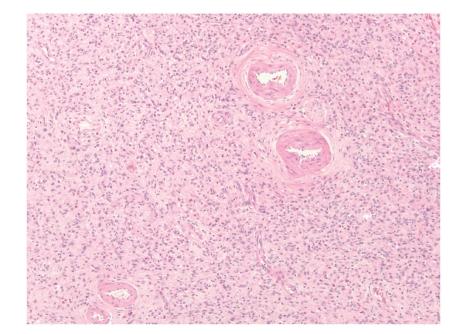

Gastrointestinal (GI) mesenchymal tumors other than gastrointestinal stromal tumor (GIST) are rare neoplasms, but they often enter the differential diagnosis of more common GI lesions. Some of these mesenchymal tumors in the GI tract have well understood molecular pathologic aspects, including desmoid tumors, inflammatory myofibroblastic tumor (IMT), clear cell sarcoma (CCS), inflammatory fibroid polyp (IFP), and synovial sarcoma (SS). Molecular pathology is fast becoming a mainstream focus in laboratories because it aids in the precise classification of tumors, may be prognostic, and may help predict response to therapy. The following review is not intended as an exhaustive summary of all mesenchymal tumors that have been reported to involve the GI tract, but instead will highlight the current knowledge of the most important non-GIST GI mesenchymal neoplasms, focusing on those tumors with well-characterized molecular pathology and how the molecular pathologic features impact current diagnostic, therapeutic, and prognostic standards.

除胃肠道间质瘤(GIST)外的胃肠道(GI)间质瘤是罕见肿瘤,但它们常被纳入更常见GI病变的鉴别诊断。胃肠道中的一些间质瘤具有已被充分了解的分子病理学特征,包括硬纤维瘤、炎性肌纤维母细胞瘤(IMT)、透明细胞肉瘤(CCS)、炎性纤维性息肉(IFP)和滑膜肉瘤(SS)。分子病理学正迅速成为实验室的主流关注点,因为它有助于肿瘤的精确分类,可能具有预后价值,还可能有助于预测治疗反应。以下综述并非旨在详尽总结所有已报道累及胃肠道的间质瘤,而是将重点介绍最重要的非GIST胃肠道间质肿瘤的当前知识,聚焦于那些具有明确分子病理学特征的肿瘤,以及分子病理学特征如何影响当前的诊断、治疗和预后标准。